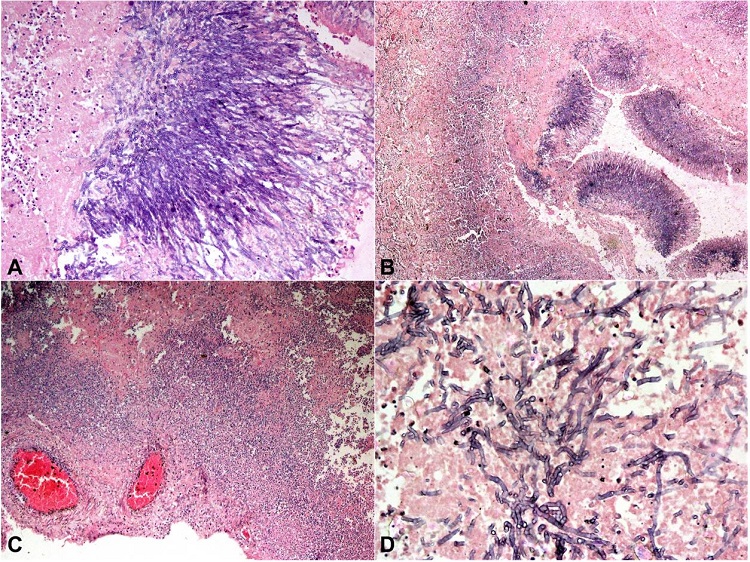

On external examination, the deceased was 173 cm in length and of average build. We observed a linear scar of 6.5 cm vertically over the left side of the forehead and the scalp’s frontal region. On reflecting the scalp, the scar was seen extending up to the periosteal layer of the skull bone. No underlying skull fracture was seen. There was no intracranial hemorrhage on internal examination; the brain was edematous weighing 1600 g (RR; 1075-1685g) and no basal exudates were seen. On the brain cut section, we noted an area of hemorrhagic necrosis in the right frontal and parietal lobes involving the corpus callosum, basal nuclei, lateral ventricle, and thalamus. The midline shift and compression of the adjacent brain parenchyma were noted. An area of necrosis with purulent exudate was seen in the cerebral cortex of the right temporal lobe (Figure 2A). Both lungs were enlarged and of hard consistency. The right lung weighed around 1050 g (RR: 360–570 g) and the left lung 1000 g (RR: 325–480 g). Multiple yellowish-white nodules were present on the surface and the cut section, and some nodules showed necrosis (Figure 2B). The hilar lymph nodes were slightly enlarged, and extensive consolidation was present in both lungs. Some cavitary lesions filled with necrotic material were present in the upper lobes of both the lungs. No pulmonary embolism or lung infarction could be seen. The heart and coronary arteries were grossly normal; the liver was enlarged, congested, and weighed 1730 g (mRR; 1540 g); the spleen and both kidneys were grossly normal except for some congestion.

On microscopic examination, sections from the lungs showed a fungal abscess showing blue staining, acutely branching septate hyphal elements consistent with the morphology of Aspergillus spp. (Figure 3A). We also noted the heavy infiltration of neutrophils in the necrotic lung tissues (Figure 3B). A section also showed a cavity filled with a fungus ball and heavy neutrophilic infiltration. Some thrombosed vessels with the invasion of fungal elements were noted. Acid-fast bacillus staining was negative, and Grocott’s silver stain showed black hyphae of Aspergillus invading the lung tissue (Figure 44B). Multiple brain sections showed foci of hemorrhagic necrosis along with heavy infiltration of neutrophils, and perivascular infiltration of inflammatory cells (Figure 3C). Multiple, blue-stained, septate fungal hyphae were identified on routine hematoxylin and eosin stain (Figure 3D). Some sections showed brain edema and thrombosed vessels. Sections from the liver showed intact liver architecture with sinusoidal dilatation (shock-related changes). Spleen and kidney sections showed congestion. The lymph nodes were normal with preserved architecture.